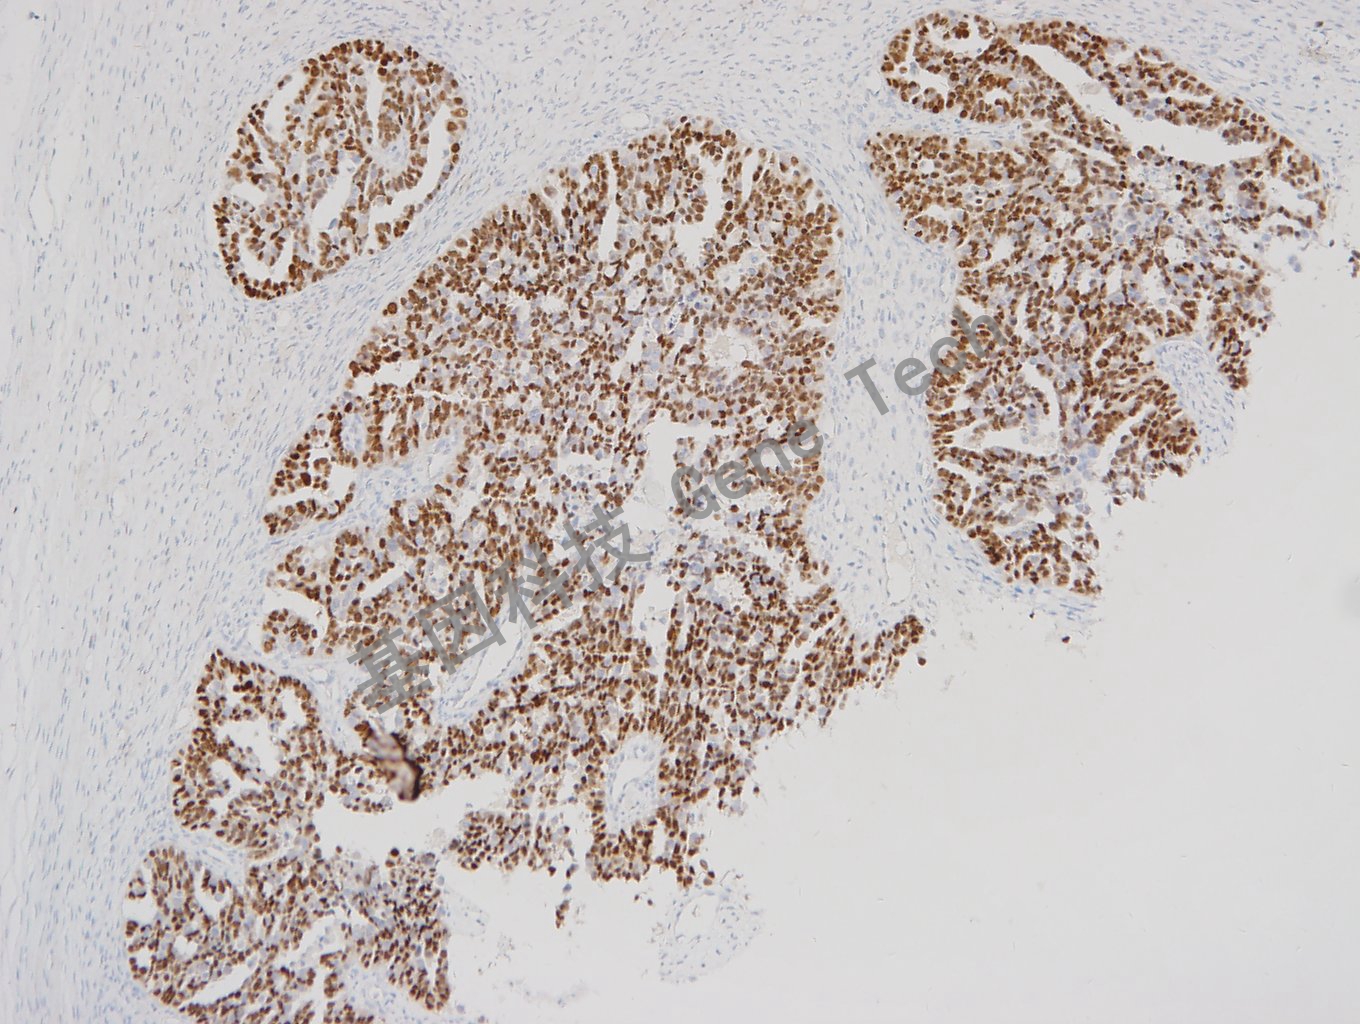

Pax-8 兔抗人 Pax-8 抗體試劑(免疫組織化學(xué))

| 預(yù)處理:高pH熱修復(fù) | 陽性部位:細胞核 | 陽性對照:腎臟/輸卵管 |

| 簡介:PAX-8(Paired box gene 8, 配對盒基因 8)是Pax核轉(zhuǎn)錄因子家族成員之一,參與甲狀腺濾泡細胞的發(fā)育和甲狀腺特異性基因的表達。表達于甲狀腺(以及相關(guān)的癌),輸卵管和卵巢囊腫的非纖毛黏膜細胞,但在乳癌和其他除了甲狀腺以外非婦科癌中不表達,使其可以作為一種新的卵巢癌標(biāo)記并用于肺和頸部腫瘤的鑒別診斷。 | ||

| 卵巢癌石蠟切片,用 PAX-8(GT2102)染色,細胞核陽性,DAB 顯色。 | ||